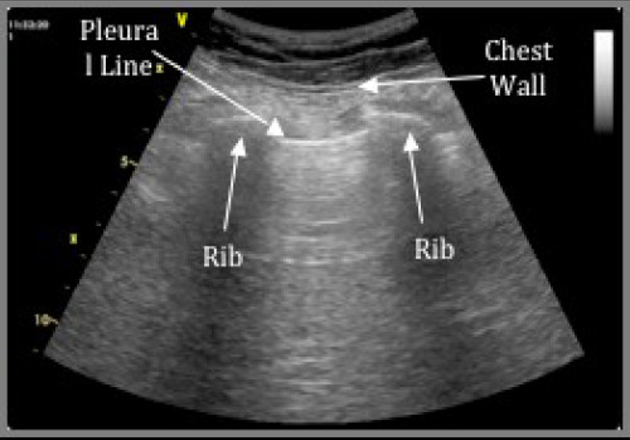

Notably, in the last 5-10 years the Extended FAST exam has become widely adopted at trauma centers, which adds assessment for pneumothorax and pleural fluid to the peritoneal and pericardial space evaluations. This EFAST exam hastens the diagnosis of important entities such as tension pneumothorax and massive hemothorax which may cause hemodynamic instability in the traumatically injured patient. Anterior lung fields are examined for “lung sliding,” which is the movement of the visceral lung pleura against the parietal chest wall pleura (Video 1). If present in the most anti-dependent region of the supine patient’s chest (Figure 20), lung sliding rules out pneumothorax with greater sensitivity than AP supine chest x-ray (REF. 6). Ultrasound can also detect as little as 20cc of pleural fluid, as seen in Figure 21.

Figure 20. Anterior thorax sagittal lung view positioned at nipple line for maximum sensitivity for detecting pneumothorax. The white pleural line is examined for lung sliding motion (Images courtesy of Matthew Lohse, MD. Baylor Scott & White-Temple)

{left is normal, right with pneumothorax}